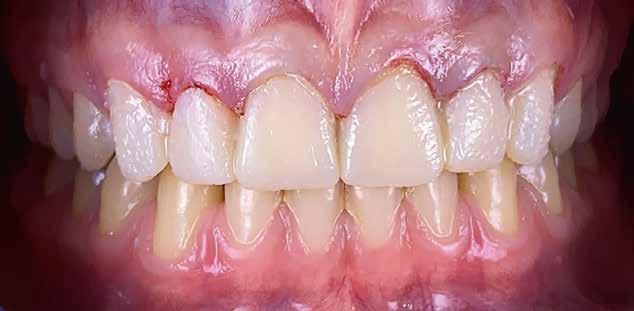

Az eset

A 75 éves páciens új fogsorokat szeretett volna. Felül nem kielégítő teljes lemezes kivehető fogsora volt, alul pedig szintén nem megfelelő részleges fogsora, néhány devitális, apikális oszteolízist és masszív szekunderkárieszt felmutató mutató maradék frontfogon. Az endodonciai beavatkozást a páciens elutasította. Ehelyett kerámiaimplantátumokra alapozott kezelést kívánt. Az úr általános egészségi állapotában panaszok mutatkoztak. A CMD-index nem volt számottevő. A DVT-vizsgálat (1. kép) alapján megállapítható a 42-es fog decens apikális oszteolízise, számottevő vertikális és horizontális csontveszteség a rágóterületen, valamint az

1. kép: Kiindulási helyzet: az OPG hat devitalizált alsó frontfogat ábrázol, részleges apikális oszteolízissel, szekunderkáriesszel, horizontális csontfelszívódással a rágóterületen.

FDOK/NICO értelmében HU alapján mért erőteljes csontsűrűség-csökkenés mutatkozik az 18, 17, 13, 23, 27 és 28 fogak régiójában.

Terápia és implantáció

Az operatív beavatkozás előtt a behelyezett fogsorokkal és azok nélkül is beszkennelték az intraorális szituációt, valamint elkészítették a fogsorok digitális másolatát. Ezután óvatosan kihúzták a maradék fogakat, és mindent előkészítettek az azonnali implantációhoz, amelynek során 6 egyrészes SDS kerámiaimplantátumot terveztek behelyezni a meglévő alveolusba a 34-43 közötti területre. Közvetlenül a behelyezést megelőzően a szék mellett még egyszer megtisztították Diener Denta Plas plazmakészülékkel (lásd 49. kép) az implantátumokat, a lehető legteljesebb csírátlanítás – így a páciens csíraterhelésének minimalizálása – érdekében (2. kép) Az alveolus ózonos tisztítását követően behelyezték a hat egyrészes SDS kerámia-implantátumot, A-PRF (saját vérlemezkében gazdag – a ford.) membránokkal megsegítve. A laborkészítésű előre mintázott elemek alapján azonnali ide-

iglenes került az implantátumokra (3. kép), majd röntgennel újólag ellenőrizték a létrejött helyzetet (4. kép)